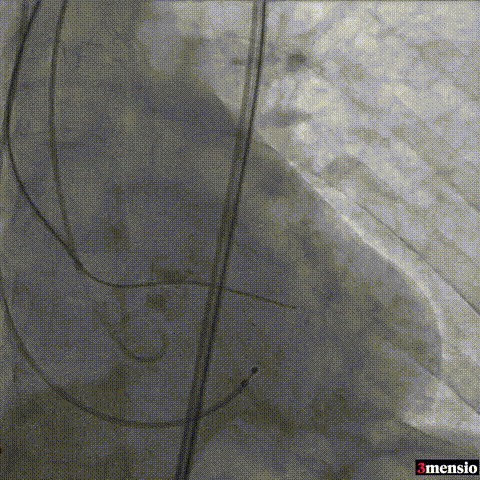

图片

输送系统过弓

瓣膜定位

瓣膜释放至工作位评估

瓣膜释放